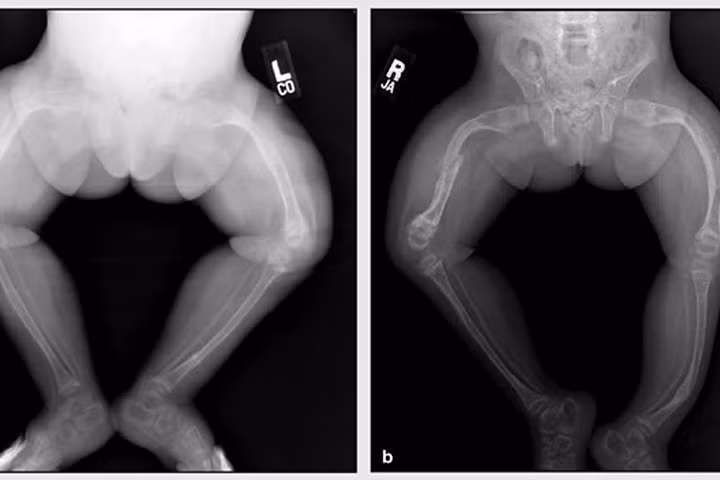

Hình chụp X.quang của một bệnh nhân xương thủy tinh. Ảnh: Physiopedia

Tại hội thảo, phương pháp chăm sóc bệnh nhân “Tạo xương bất toàn” (xương thủy tinh) bằng Đông - Tây y kết hợp đã được giới y học quan tâm.

Trình bày tham luận, BS Trần Văn Năm – Phó Viện trưởng Viện Y học dân tộc TP.HCM nhận định, đây là loại bệnh chưa thể điều trị khỏi, mà hiện chỉ mới dừng ở mức tập vật lí trị liệu, sử dụng thuốc bổ sung can xi để tăng cường cho xương.

Qua 6 năm điều trị, chăm sóc bệnh nhân xương thủy tinh, ông cho biết, việc kết hợp giữa Đông và Tây y trong điều trị bệnh đang mang lại kết quả cao.

Qua điều trị thực tế 100 trẻ bị xương thủy tinh tại quận 12, BS Năm nhận thấy 95% trẻ hết đau sau 30 ngày chăm sóc, giảm từ 57-78% tần suất gãy xương, phục hồi vận động đạt 36 - 66% và đa số tự đi lại được.

Từ những thành tựu ban đầu, BS.Trần Văn Năm nhấn mạnh, cần phải kết hợp điều trị giữa Y học cổ truyền và Y học hiện đại để mang lại hiệu quả tốt cho người bệnh.